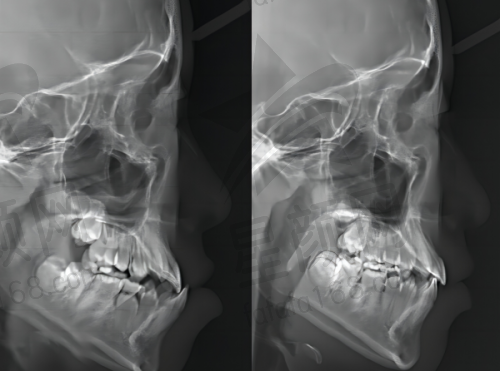

此外,私立口腔在设备和技术的引进上更加灵活。洪志口腔不断更新精良的口腔诊疗设备,如数字化口腔扫描仪、口腔CBCT等,这些设备能够更精细地诊断口腔问题,为治疗提供有力的支持。同时,诊所还积极引进国内外精良的口腔治疗技术,确保患者能够享受到良好质的口腔医疗服务。

即刻种植牙是洪志口腔的一项特色推荐项目。对于牙齿缺失的患者来说,传统的种植牙方式需要等待较长的时间,给患者的生活和饮食带来诸多不便。而即刻种植牙技术则可以在拔牙后立即植入种植体,大大缩短了治疗周期。

在洪志口腔,医生会在拔牙后对患者的牙槽骨进行评估,根据患者的具体情况制定个性化的即刻种植方案。医生们拥有丰富的临床经验,能够熟练操作即刻种植牙技术,确保种植体的稳定性和成功几率。术后,患者修复快,能够更快地修复正常的咀嚼功能和美观。